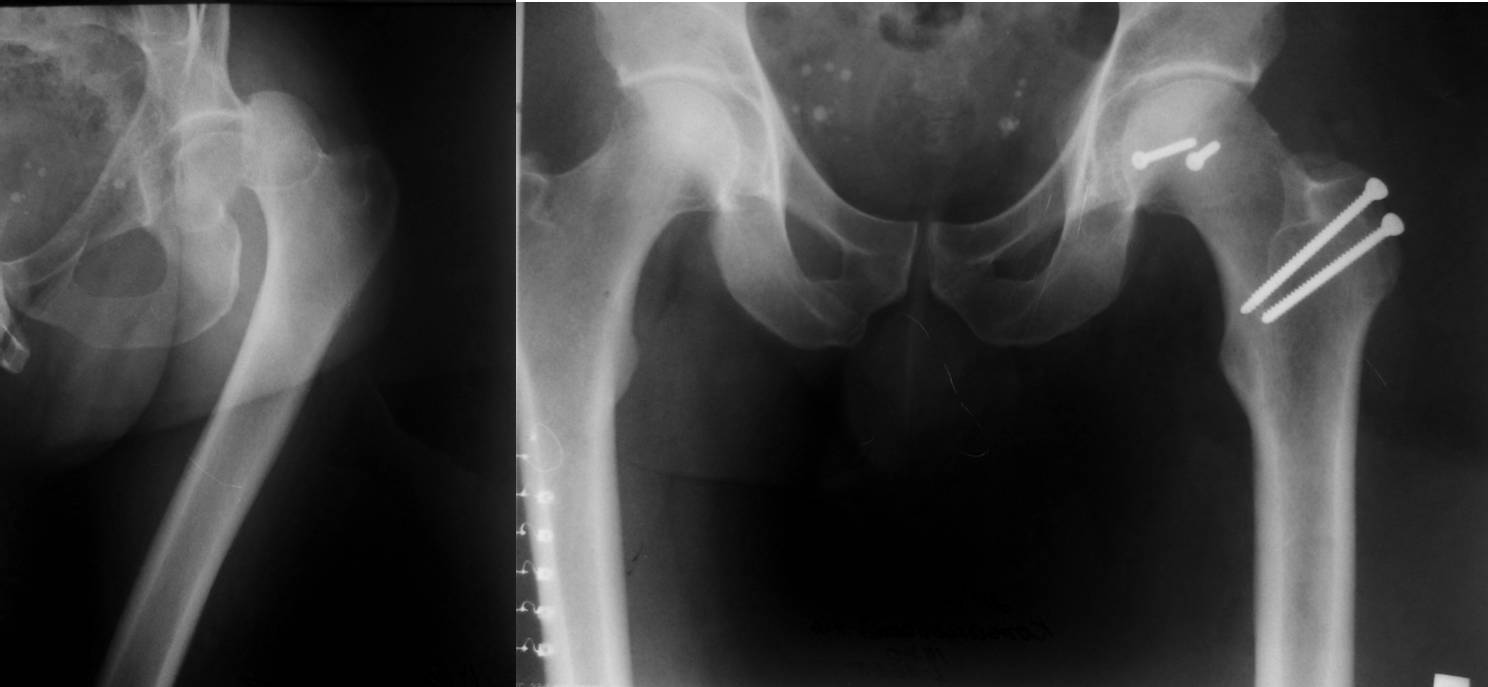

Поскольку имеется перелом края вертлужной впадины, перелом относится к типу Pipkin IV. Ну, это так, к слову. Больной до шестидесяти лет, поэтому методом выбора должна быть открытая репозиция перелома, остеосинтез винтами. Головки винтов должны быть заглублены ниже уровня суставного хряща. Нет на представленной КТ срезов в корональной плоскости, поэтому невозможно точно определить имеющийся дефект задневерхнего края вертлужной впадины и, следовательно, необходимость репозиции и фиксации её отломанного фрагмента. Лучшим доступом в данном случае является латеральный доступ с отсечением большого вертела по Ganz с вывихом головки бедренной кости в рану. Доступ позволяет не только без проблем выполнить репозицию и фиксацию не только перелома головки бедренной кости, но и края вертлужной впадины в случае необходимости. Доступ подробно описан в «Rockwood And Green's Fractures In Adults».

Один случай из личного опыта, когда использовался этот доступ – во вложенном файле.

С уважением, VlaD.